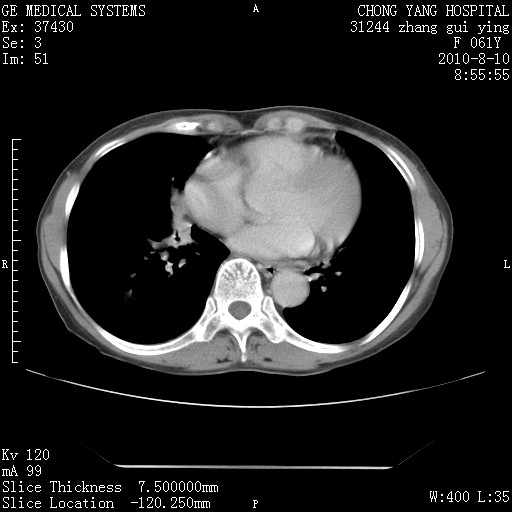

标题: CT28314:F61Y胸部增强,发热咳嗽一周入院,后面的为一周前平 [打印本页]

标题: CT28314:F61Y胸部增强,发热咳嗽一周入院,后面的为一周前平

1、支持考虑右侧中央型肺癌伴右肺中叶节段性不张及下叶支气管黏液痰栓    2、左肺上叶舌段感染。

支持3楼意见,还要考虑:纵隔及肺门淋巴结转移、右侧少量胸腔积液。

确切的说:1:右肺下叶中心型肺癌侵及中叶支气管并中叶不张,纵膈淋巴结转移。2:左肺舌叶炎症。3:右侧胸腔少量积液

块影平扫32hu,动静脉期62-70hu.

1:右肺下叶中心型肺癌侵及中叶支气管并中叶不张,纵膈淋巴结转移。2:左肺舌叶炎症。3:右侧胸腔少量积液。支持!

右肺下叶内基底段近膈不规则肿块,考虑右肺下叶周围型肺癌可能性大。

考虑右下肺肺癌,纵隔淋巴结转移i。

右肺下叶中心型肺癌侵及中叶支气管并中叶不张,纵膈淋巴结转移。2:左肺舌叶炎症。3:右侧胸腔少量积液